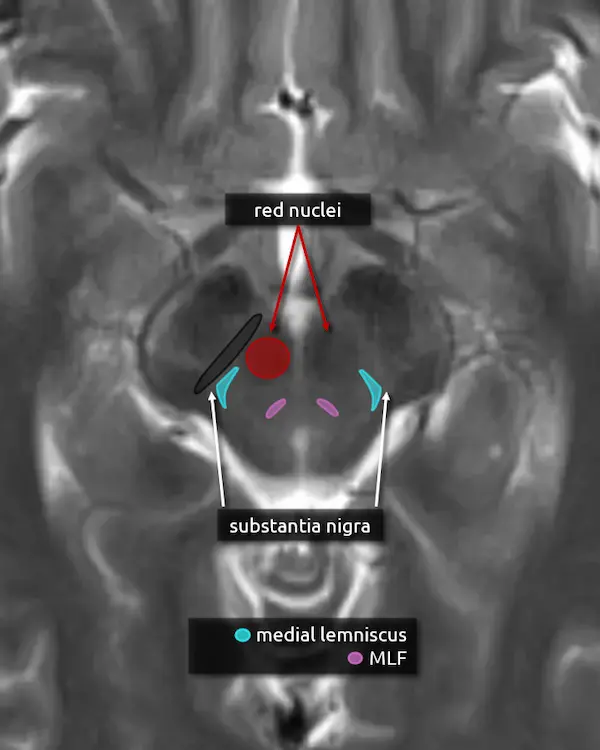

3. Red nucleus

The red nucleus is a component of the extrapyramidal motor system. It takes input from the cerebellum (via the superior cerebellar peduncles), motor, premotor, and frontal cortices and projects to the contralateral cervical spinal cord and, to a lesser extent, the ipsilateral inferior olivary nucleus (see rostral medulla below) via the rubrospinal tract. The red nuclei are dark on T2-weighted MRI images, producing the eyes of the "Mickey Mouse" appearance of the upper midbrain.

Focal damage to the red nucleus is rare but may occur in paramedian midbrain syndrome (Benedikt syndrome). Lesions in this region characteristically cause contralateral tremor, ataxia, and involuntary limb movements (choreoathetosis). The red nucleus is also used as a border for the localization of posturing; decerebrate posturing usually results from lesions at or below the red nucleus and decorticate posturing from lesions above.

4. Substantia nigra

The substantia nigra is a large nucleus at the base of the cerebral peduncle that spans the midbrain. It is a major component of the extrapyramidal motor system and has bidirectional connections between the striatum (caudate and putamen), forming the nigrostriatal pathway. It is composed of two areas: the pars compacta and the pars reticulata.

Loss of dopamine producing neurons in the pars compacta is a defining feature of Parkinson's disease.

5. Medial lemniscus

The medial lemniscus is an ascending sensory pathway that spans the entire brainstem, originating at the nucleus gracilis and cuneatus (see level 5) in the medulla and ending at the primary sensory nucleus of the thalamus: the ventral posterolateral nucleus (VPL). It begins medially in the medulla and becomes more lateral at the level of the midbrain, located in close proximity to the substantia nigra. It is responsible for vibration sensation, fine touch, and proprioception.

Lesions involving the medial lemniscus may cause contralateral loss of vibration sensation and joint position sensation on physical exam with symptoms of numbness and paresthesias.

6. Medial longitudinal fasciculus (MLF)

The MLF is an ascending and descending pathway responsible for coordinating eye movements. It connects all of the cranial nerve nuclei that innervate the extraocular muscles (CN III, IV, and VI) as well as the vestibulocochlear nuclei (CN VIII). The MLF spans the entire brainstem, however lesions producing visual symptoms will probably be in the midbrain or pons.

There are characteristic syndromes that result from damage to the MLF, most commonly internuclear ophthalmoplegia (INO) or INO-plus syndromes. A common clinical scenario is a patient with multiple sclerosis who develops a demyelinating lesion along the MLF in the midbrain or pons and presents with bilateral INO.